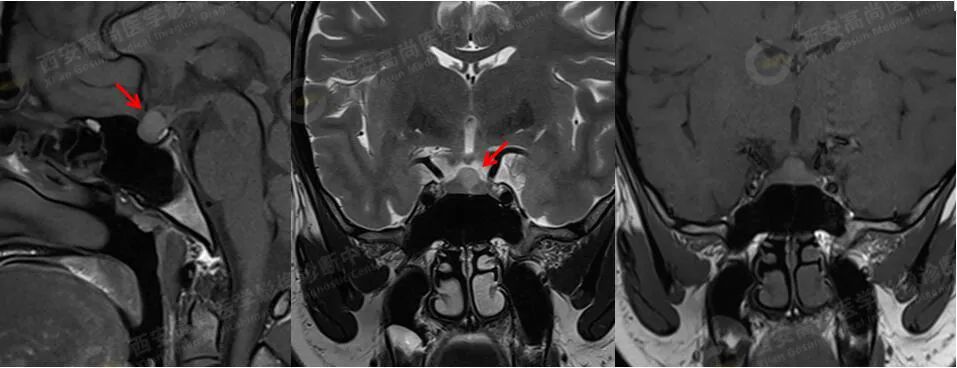

MRI 平扫+增强:垂体前叶上缘见大小约 8 mmX7 mmX7 mm 的类圆形稍短 T1 稍长 T2 信号,边缘欠清晰,视交叉轻度受压,垂体前叶上缘病灶延迟期呈稍低信号,边缘清晰;

诊断:垂体前叶上缘类圆形病灶,考虑 Rathke 囊肿,建议定期复查。